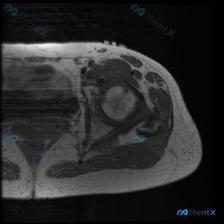

整理了一例有意思的影像临床矛盾病例,把分析思路分享给大家,一起来讨论。 病例基本信息 临床观察提示:髋部存在软组织积液 提供检查:单张髋部MRI T1序列轴位图像 影像阅片结果 1. 骨骼结构:股骨头形态圆整,骨皮质轮廓完整,未见明显骨质中断;股骨头及近端股骨骨髓信号呈中等偏高,符合正常T1加权像骨...